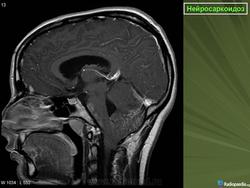

ID: 17921 Neurosarcoidosis Dr Frank Gaillard - 25 May 2012 The case demonstrates typical features of neurosarcoidosis, which are of...

Случай 1: с участием лептоменинга

Случай 2: с участием паренхимы

Случай 3

Случай 4: вокруг гипофизарного стебля

Случай 5: вовлечение спинного мозга

Случай 6: вовлечение гипофизарного стебля

Рисунок 8

Рисунок 8 Нейросаркоидоз.